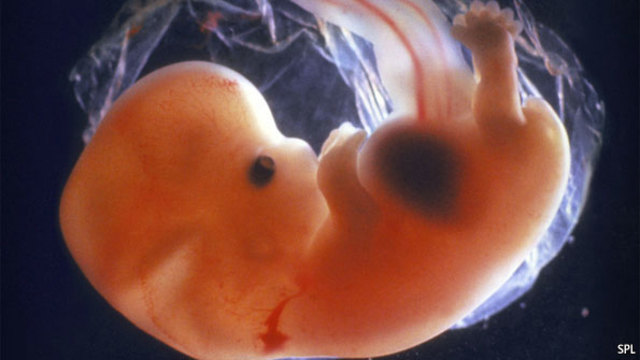

• First Trimester (four weeks)

First Trimester (four weeks)

The fetus is a zygote, is one forth of an inch long, has a heart beat, and pumps blood to the liver and aorta. The mother will experience a missed period, fatigue, dizziness, nausea, and may be sensitive to certain smells.